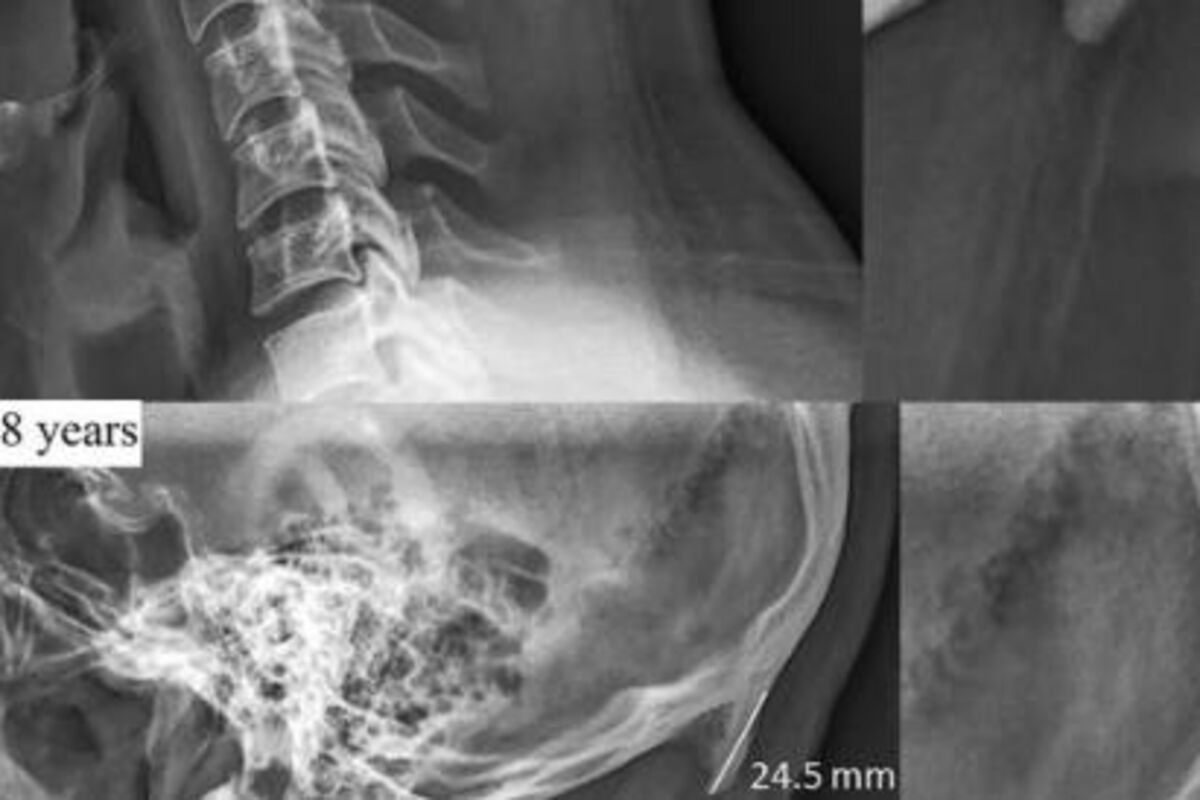

Slike sa rentgena koje su objavil istraživači iz Australije pokazuju da zbog toga što smo stalno pogrbljeni nad telefonom, naša lobanja počinje da razivija dodatni rast kostiju.

Sudeći po njihovoj studiji, sve veći broj ljudi, posebno mlađih, ima izraštaj na dnu lobanje.

Ovi izraštaju su posmatrani kao retki kada su prvi put otkriveni pre 200 godina, ali sada izgleda da možemo da zaista osetimo kosti, pa čak ih i vidimo ko ćelavih ljudi.

Ovaj izraštaj je najčešći kod ljudi starosti između 18 i 30 godina, a izbočine su rezultat načina na koji gledamo ekrane telefona i kompjutera.

Nakon skeniranja više od 1.000 lobanja ljudi starosti između 18 i 86 godina, dr David Šahar sa Univerziteta Sunčane obale u Kvinslendu, tvrdi da je ova promena izazvana dodatnim naporom na delove tela koje ne koristimo često.